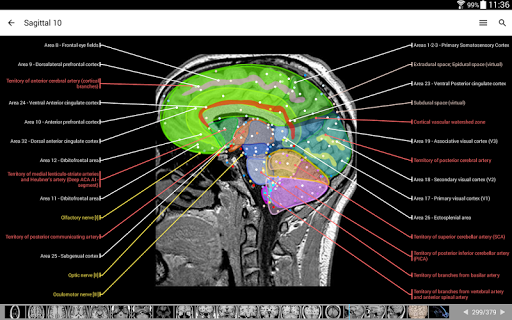

e-Anatomy tiene más de 26 000 imágenes que contienen series de imágenes en vistas axiales, coronales y sagitales, así como radiografías, angiografías, imágenes de disección, gráficos anatómicos e ilustraciones. Todas las imágenes médicas fueron etiquetadas cuidadosamente, más de 967 000 etiquetas disponibles en 12 idiomas, incluida la Terminologia Anatomica latina.

- Toque las etiquetas para mostrar las estructuras anatómicas

- Seleccione las etiquetas anatómicas por categoría